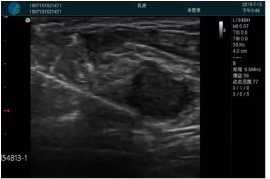

可視化穿刺引導(dǎo)

M20實(shí)時(shí)引導(dǎo):向包塊后方間隙注射利多卡因

清晰顯示腺體內(nèi)低回聲快影,邊界清晰,包膜較光滑

確定進(jìn)針路徑并實(shí)時(shí)監(jiān)測(cè)抽吸針與腫塊位置關(guān)系

抽吸針進(jìn)入腫塊內(nèi)部進(jìn)行旋切

抽吸過(guò)程中可見(jiàn)腫塊明顯縮小,并根據(jù)腫塊位置改變針道位置

抽吸旋切后再進(jìn)行超聲復(fù)查,原腫塊區(qū)域未見(jiàn)殘留組織及出血

超聲引導(dǎo)下抽吸旋切取出的腫塊組織